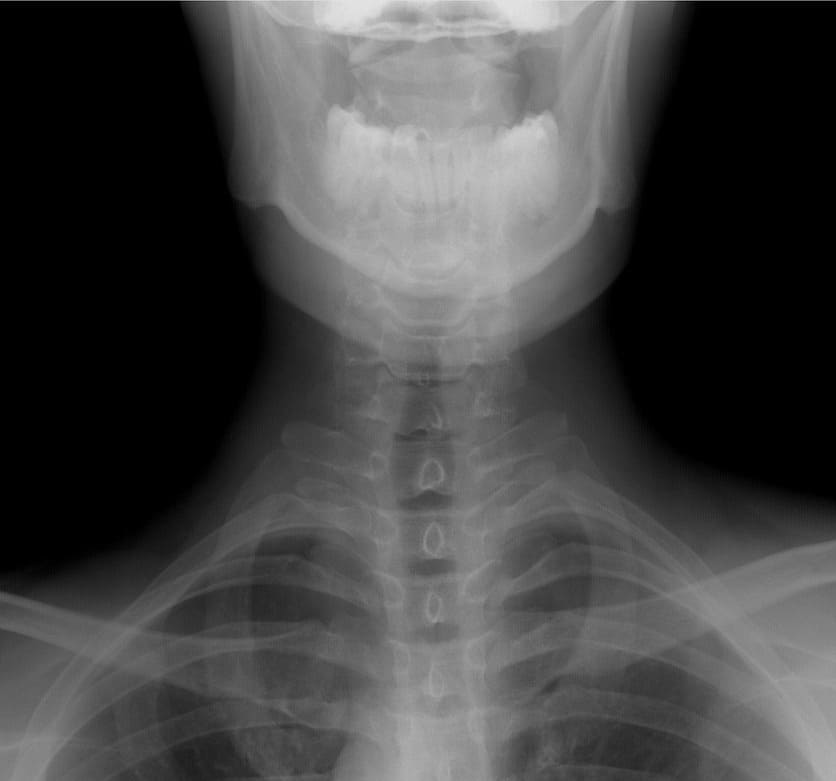

병원 가면 어떤 검사를 하나요? 정확한 진단법

목디스크가 의심되어 병원을 방문하면, 여러 가지 검사를 통해 정확한 진단을 받게 돼요. 2025년 현재 최신 기술로 더 정밀한 진단이 가능하답니다.

| 엑스레이(X-ray) | 목뼈의 배열이나 전체적인 모양을 쉽게 확인할 수 있어요. |